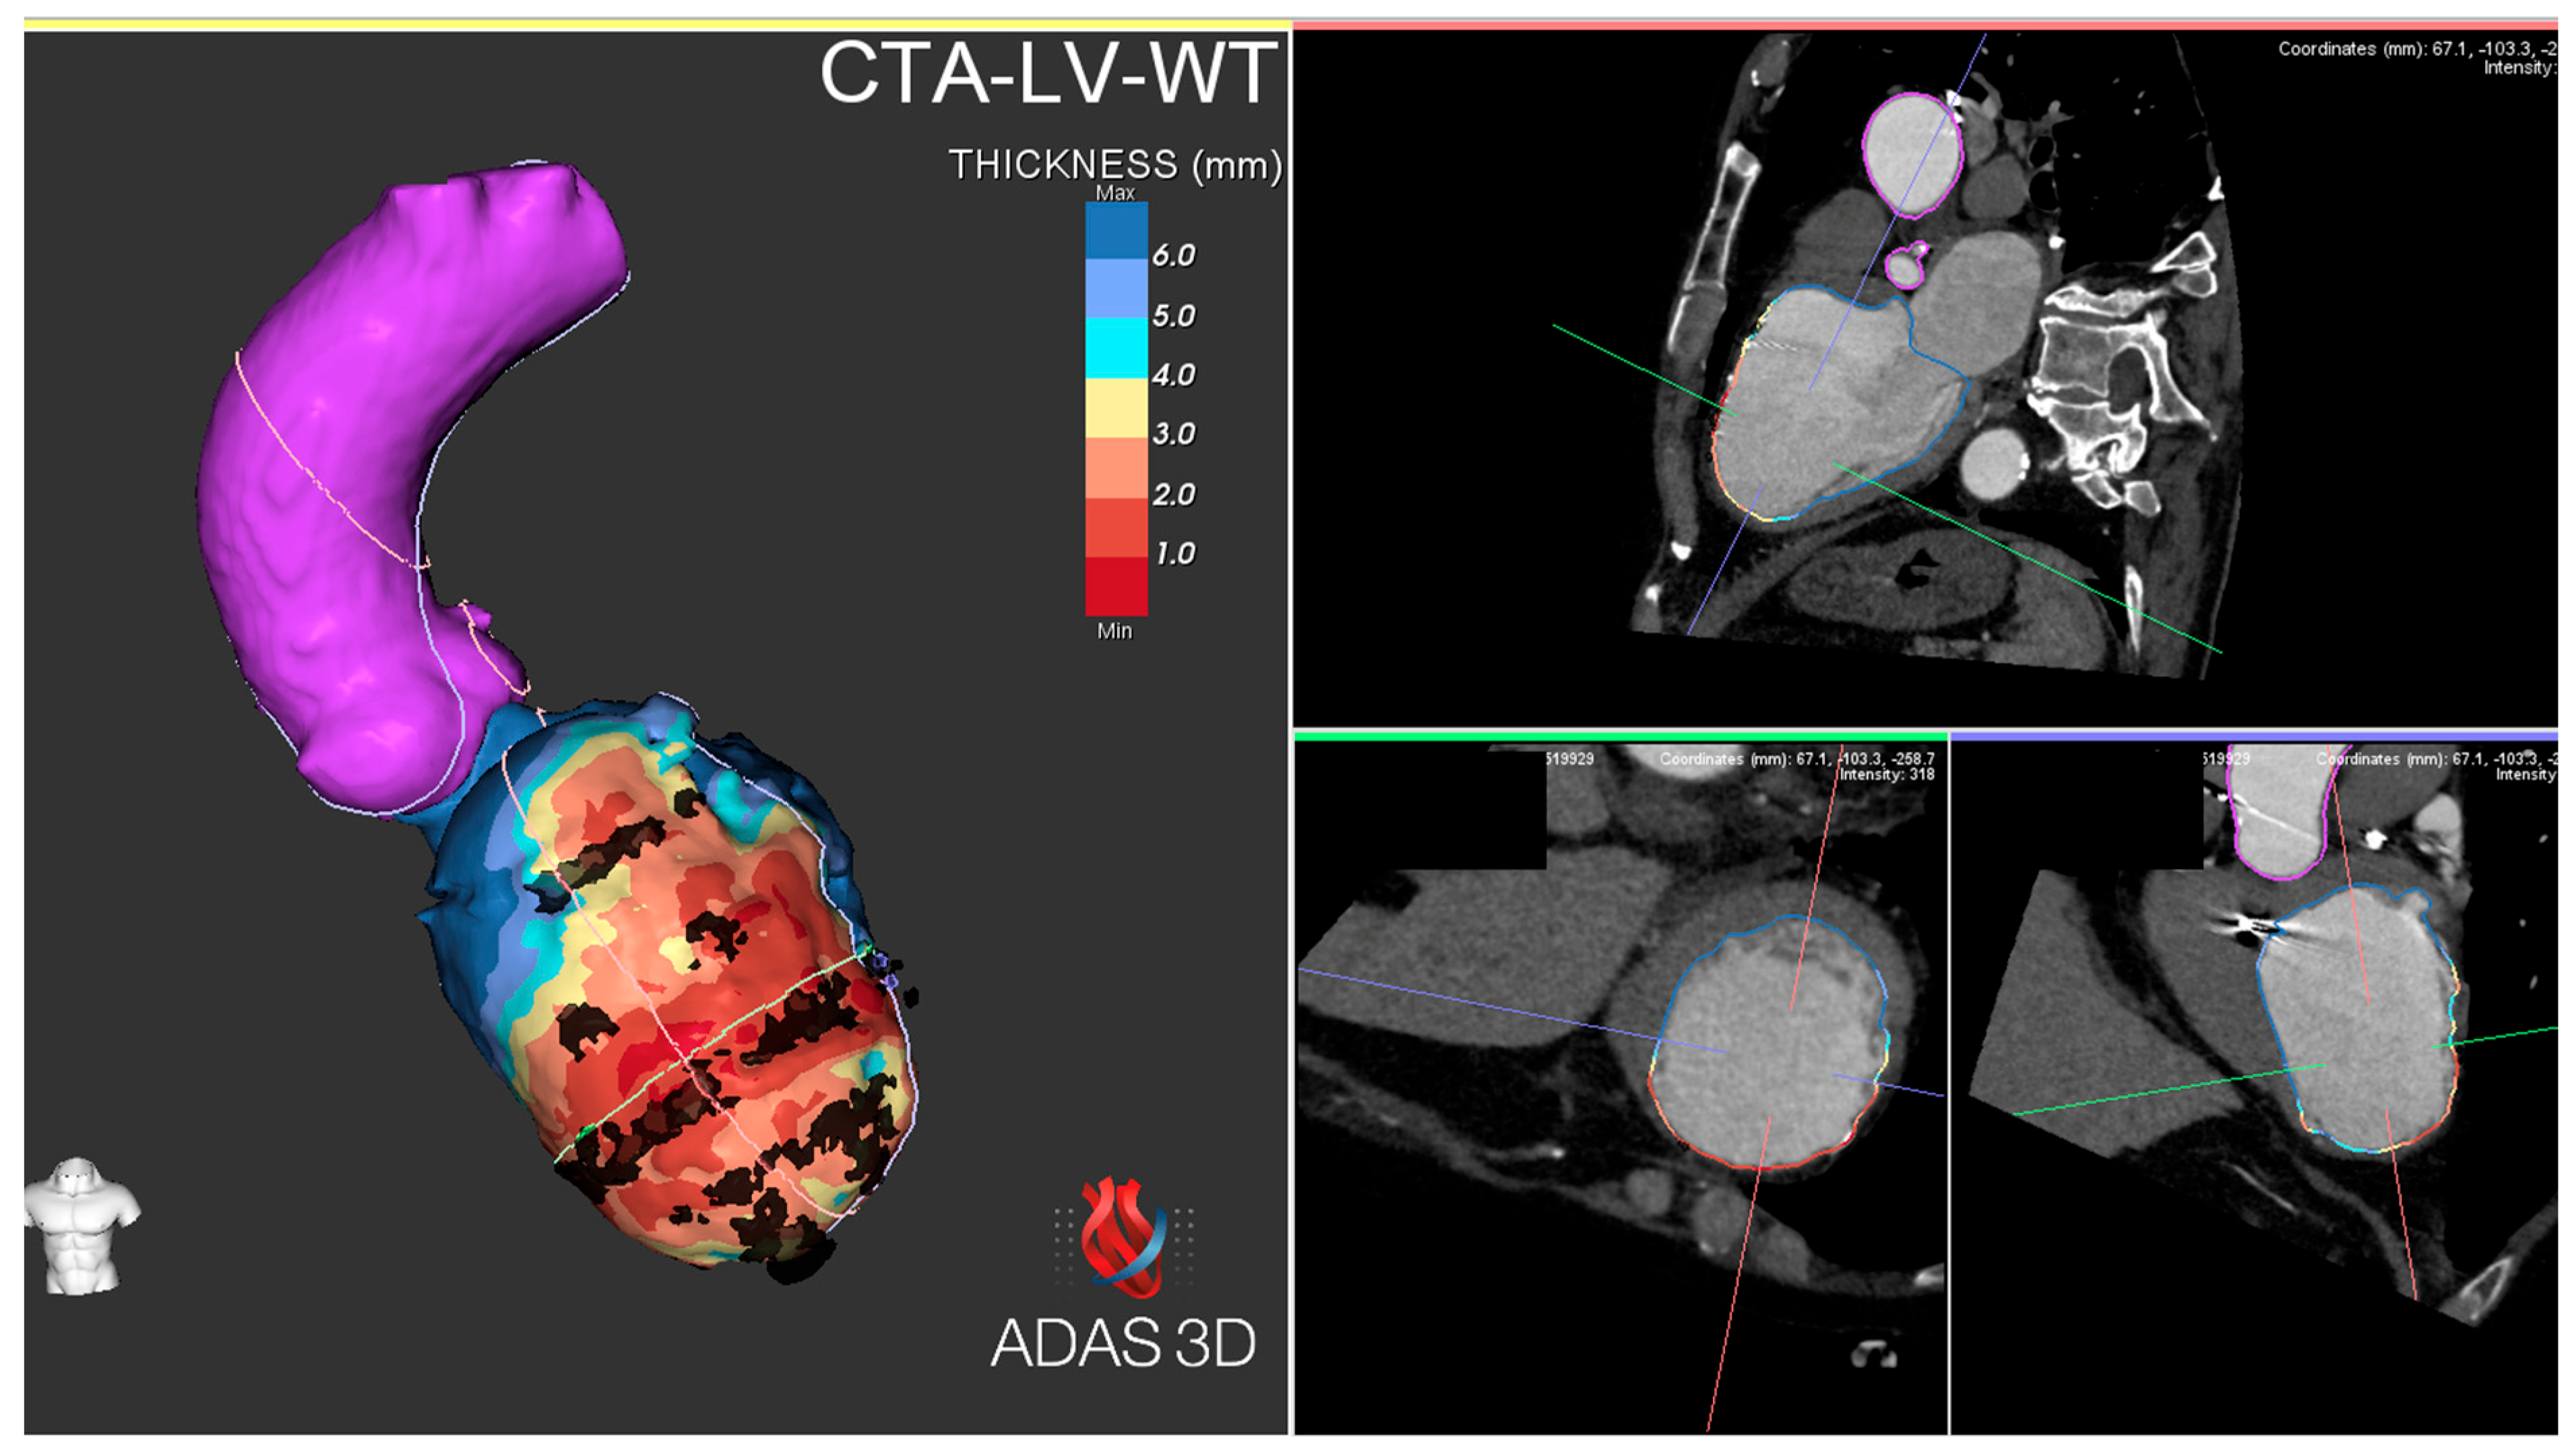

4. Intraprocedural Imaging: Focus on CT and CMR

- Komatsu, Y.; Cochet, H.; Jadidi, A.; Sacher, F.; Shah, A.; Derval, N.; et al. Regional Myocardial Wall Thinning at Multidetector Computed Tomography Correlates to Arrhythmogenic Substrate in Postinfarction Ventricular Tachycardia: Assessment of Structural and Electrical Substrate. Circ Arrhythm Electrophysiol. 2013, 6, 342–350. [Google Scholar] [CrossRef]

- Takigawa, M.; Duchateau, J.; Sacher, F.; Martin, R.; Vlachos, K.; Kitamura, T.; et al. Are wall thickness channels defined by computed tomography predictive of isthmuses of postinfarction ventricular tachycardia? Heart Rhythm 2019, 16, 1661–1668. [Google Scholar] [CrossRef]